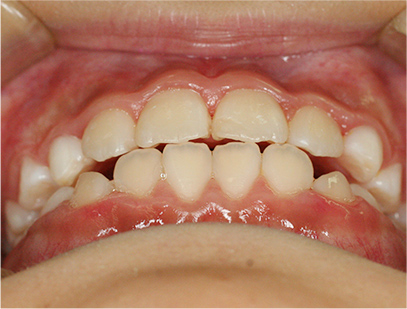

前歯部の開咬とデコボコ

前歯部が咬んでいないことを主訴として来院されました。精査、診断の結果「前歯部にデコボコを伴う開咬」と診断されました。

下の歯の裏側に舌が出ないように矯正装置を取り付け、そして上の歯には取り外しのできる矯正装置を装着して、側方に拡大を行います。

取り外しのできる矯正装置、舌が出せなくなる矯正装置(フェンス)

治療期間は、患者様の努力とお母さまの協力が得られて1年間で終了しました。